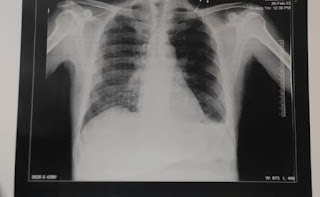

Xray chest

On 6/3/23